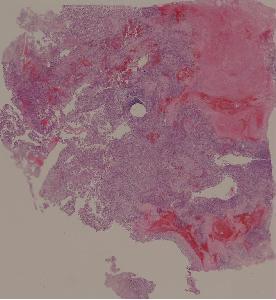

34.骨肉瘤